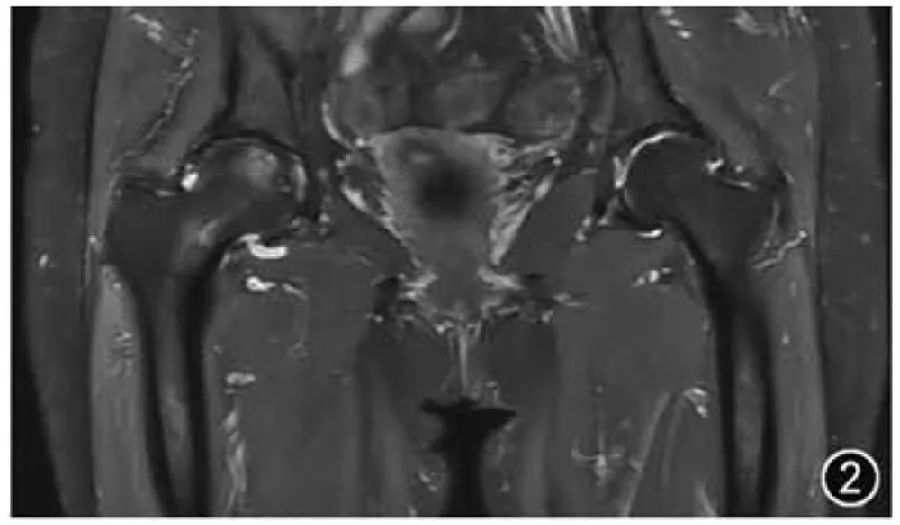

ОА является наиболее частым заболеванием тазобедренного сустава и является результатом дегенерации суставного хряща, субхондральной кости и мягких тканей. МРТ может помочь выявить ОА тазобедренного сустава на ранней стадии и может использоваться для последующей оценки. Вообще говоря, ОА тазобедренного сустава диагностируется врачом и оценивается как легкий, средний и тяжелый. Другие более подробные системы оценки тазобедренного сустава на основе МРТ в основном используются для исследований, а не для рутинных клинических отчетов. Общие признаки визуализации, которые требуют внимания при ОА тазобедренного сустава, должны включать: морфологию костей вертлужной впадины, головки и шеи бедренной кости, гиперплазию костей и остеофиты, хрящевые и субхондральные кисты и отек, а также повреждение вертлужной впадины, суставной выпот, синовит и рыхлые тела и т. д. Следует отметить, что истончение суставного хряща врач может оценить визуально, без измерения (рис. 2).

Рисунок 2. МРТ-изображения двустороннего остеоартрита тазобедренного сустава. Корональный Т2-ВИ показывает двустороннее сужение тазобедренных суставов и гиперплазию костей, а на головке правой бедренной кости можно увидеть очаговый отек костного мозга под суставной поверхностью.